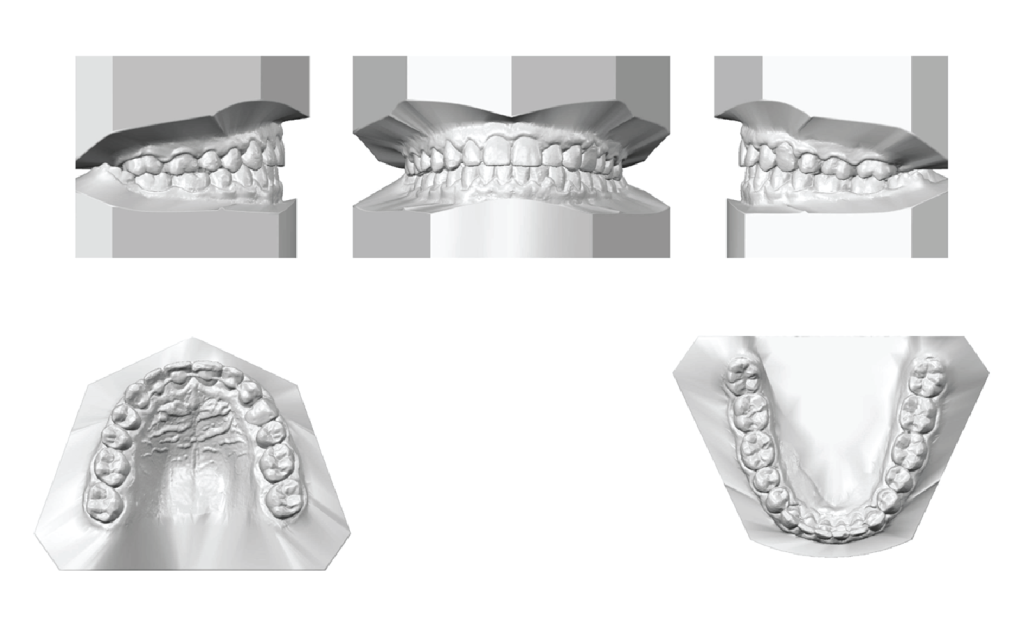

Digital cast analysis (Figure 2) indicated a Class I molar and canine relationship on both the right and left sides. The overjet was between 2 and 4 mm, while the overbite ranged from 2 to -3.2 mm. Both the maxillary and mandibular dental arch widths were within normal limits, with the maxillary inter-canine and inter-molar widths measuring 35.6 mm and 43.5 mm, respectively. The mandibular inter-canine and inter-molar widths were 26.3 mm and 36.1 mm, respectively. Mild crowding was observed in the mandibular arch, with a dental arch space deficiency of 3.3 mm in the mandible. Additionally, a Bolton discrepancy of 0.5 mm was noted due to anterior maxillary teeth excess. Furthermore, marginal ridge discrepancies were present on both maxillary and mandibular arches.

Figure 2: Pre-treatment digital casts. Pre-treatment digital casts show a Class I molar and canine relationship on the right side, a Class I molar relation on the left side, and a Class II canine relation on the left side with an open bite on the maxillary left central, lateral, and canine. Both maxillary and mandibular dental arch widths were mildly constricted, with mild crowding in the mandibular arch. We can also observe marginal ridge discrepancies on both maxillary and mandibular arches, and a Bolton discrepancy due to a maxillary anterior teeth excess.